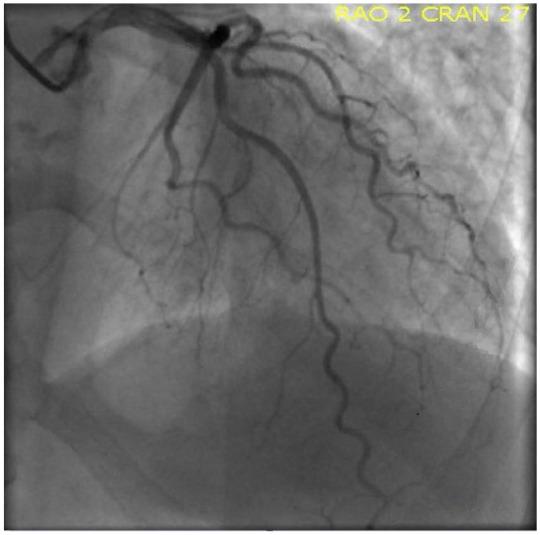

The incidence of mechanical valve thrombosis (MVT) is around 0.4 per 100 patient-years. Mitral valve thrombosis has a higher incidence than aortic valve thrombosis with a nearly 5-fold increase. Various factors contribute to MVT. The most common cause of valve thrombosis is poor adherence/disruption of anticoagulation therapy. Low cardiac output is known to increase the risk of prosthetic valve thrombosis. Other factors such as diabetes, hypertension, and other patient comorbidities might also play a role. Decreased flow promotes hypercoagulability. Lower pressure in the left atrium (and higher velocities in the left ventricle) can partially contribute to the higher incidence of mitral MVT versus aortic MVT. The presenting symptoms usually depend on the severity of the valve thrombosis; nonobstructive valve thrombosis patients have progressive dyspnea, signs of heart failure, and systemic embolization with strokes being the most common complication. In this article, we present a case of a middle-aged woman with a history of mitral and aortic mechanical prosthesis who presented with an ST-segment elevation myocardial infarction and pulmonary edema due to mechanical aortic valve prosthesis thrombosis. She had an isolated mechanical aortic valve prosthesis thrombosis with intact mitral valve, which, to the best of our knowledge, has not yet been described. We performed a literature review by searching PubMed and Embase using the keywords "mechanical valve," "thrombosis," "aortic," and "mitral," our search did not show similar cases.

机械瓣血栓形成(MVT)的发生率约为每 100 患者年 0.4 例。二尖瓣血栓形成的发生率高于主动脉瓣血栓形成,几乎增加了 5 倍。多种因素导致 MVT。瓣膜血栓形成最常见的原因是抗凝治疗的依从性差/中断。已知低心输出量会增加人工瓣膜血栓形成的风险。其他因素,如糖尿病、高血压和其他患者合并症,也可能起作用。血流减少会促进血液高凝。左心房压力降低(左心室速度升高)可能部分导致二尖瓣 MVT 与主动脉 MVT 的发生率较高。临床表现通常取决于瓣膜血栓形成的严重程度;非阻塞性瓣膜血栓形成患者逐渐出现呼吸困难、心力衰竭体征和全身性栓塞,其中中风是最常见的并发症。在本文中,我们报告了 1 例中年女性,有二尖瓣和主动脉机械假体的病史,因机械主动脉瓣假体血栓形成而出现 ST 段抬高型心肌梗死和肺水肿。她患有孤立性机械主动脉瓣假体血栓形成,二尖瓣完整,据我们所知,这种情况尚未被描述。我们通过在 PubMed 和 Embase 上使用关键词“机械瓣”、“血栓形成”、“主动脉”和“二尖瓣”进行了文献回顾,我们的搜索没有显示出类似的病例。